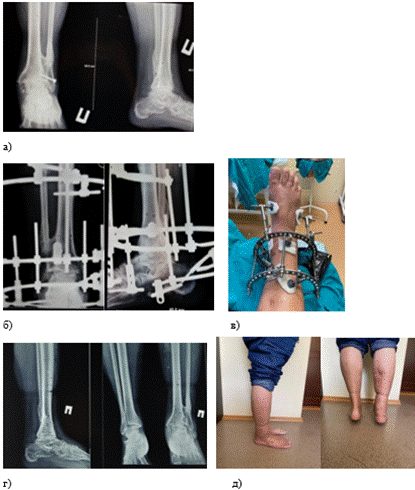

Клинический пример 1. Пациент Г., 1958 г. р. Диагноз при поступлении: посттравматический деформирующий артроз левого голеностопного сустава со стойким болевым синдромом. Сросшийся перелом медиального края левой большеберцовой кости, латеральной лодыжки после травмы 10-летней давности (10.09.2011 г.). Операция: Открытый компрессионный артродез левого голеностопного сустава 08.04.2021 г. демонтаж аппарата 27.07.2021 г. После хирургического вмешательства был проведен курс восстановительного лечения с регулярным контролем состояния. Исход лечения оценен как положительный. Работа нижней конечности, включая способность к поддержанию веса и осуществлению движений, приведена в норму; болевые ощущения устранены в полном объеме (рис. 2 а-д).

Рис. 2. Этапы и исходы хирургического лечения АВФ пациента Г., 1958 г. р.: а − рентгенограмма деформирующего артроза голеностопного сустава; б − рентгенограммы в процессе лечения в аппарате внешней фиксации (АВФ); в − фотография конечности в аппарате; г − рентгенограмма результата лечения − сформированный анкилоз голеностопного сустава; д − фотографии результатов лечения − восстановленная функция нижней конечности. Составлено авторами